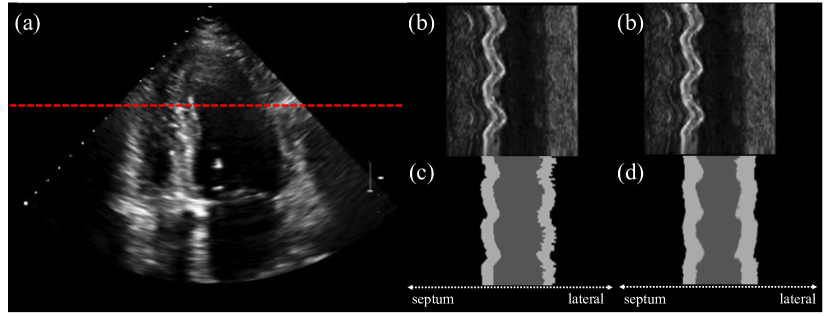

Refer to caption

Figure 6: Impact of cross-frame attention on a patient exhibiting rapid radial motion and a high heart rate. (a) B-mode image (b) radial image cut spanning the entire time sequence (c) and (d) segmentations without and with cross-frame attention, respectively.

Spatio-Temporal Apater Design In this section, we investigate the impact of spatio-temporal adapter designs on the performance of our method. We conducted ablation experiments to examine the effects of cross-frame attention in our model. Our experiments demonstrate that the inclusion of cross-frame attention leads to a 0.2% improvement in Dice and a 0.03 increase in temporal smoothness, showcasing its positive impact on our method’s performance. Figure 6 provides a visual comparison of MediViSTA across frames, emphasizing the presence of ambiguous boundaries on the lateral side. Nevertheless, our model successfully captures temporal information along the time axis, resulting in segmented images with enhanced temporal smoothness. This observation highlights the interdependence between adjacent frames, where each frame significantly influences its neighboring frames.